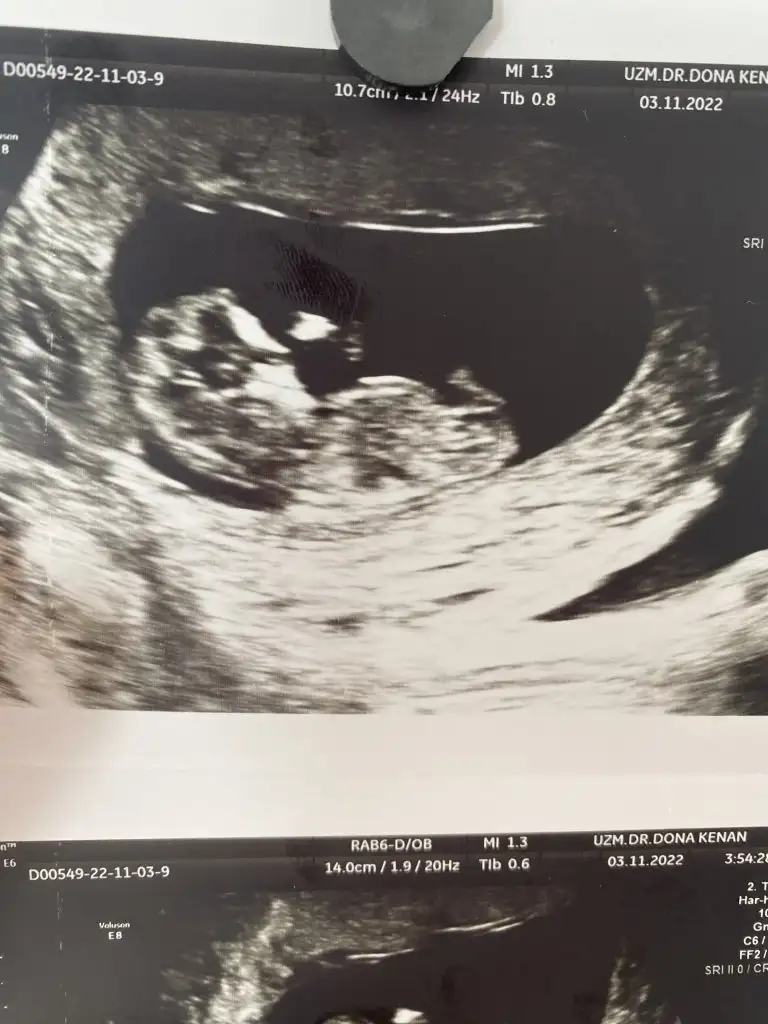

Onda 10 hafta 5günlük büyük usg dekiDaha küçük hafta usg si var bide

Bende 11+2 deyim doktorum tahminde bulundu ve erkek dedi ama ben hiç erkek hissetmiyorum bu zamana kadar sivilce çıkmayan yüzümde alnımda 4 tane sivilce çıktı ultrason fotoğrafını bırakıyorum Kızlar bana da bir tahmin de bulunsanızMerhaba ben bugün itibariyle 14 haftalık gebeyim. 11. Haftada perinatolog erken ama bebeğin erkeğe benziyor dedi. 12 de doktorum da aynı şeyi söyledi. Ama 12+4 de gittiğim ayrıntılı ultrasonda nub teorisine göre yüzde 70 kız dedi. Hatta biz erkeğe benzettiler deyince yok yok kız çoğunlukla da bu teori doğru çıkıyor dedi. Biz de kız dedik herkese. Bugün 14 hafta oldum kontrolümde kendi doğum uzmanım sırtı dönük ama bşr çıkıntı var kordon da olabilir erken ama ben erkek tahmin ediyorum dedi. Yine de kordonla karışabilir dedi. Artık iyice kafam karıştı. Sizin fikriniz ne? Benzer birşey yaşayan varsa paylaşır mısınız? Ultrason fotoğrafı bırakıyorum anlayan baksın lütfen.